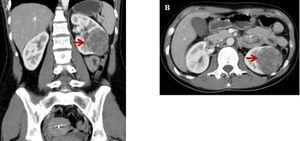

Dos años más tarde, estando medicada con enalapril, losartán y amlodipina, ingresa a la guardia de nuestro hospital consultando por cefalea occipital y debilidad muscular de varios días de evolución. Se constata PA de 220/140 mmHg. En sus estudios iniciales se detectó hipokalemia de 2 mEq/l, creatinina plásmatica de 0,6 mg/dl y urea plasmática de 25 mg/dl. La ecografía renal evidenció una imagen nodular sólida, corroborada por tomografía computarizada abdominal contrastada, donde se observó una voluminosa formación ocupante de espacio, sólida, en sector interpolar y polo inferior del riñón izquierdo de 65 mm de diámetro, hipovascularizada (figura 1). El Doppler de arterias renales y el ecocardiograma no mostraron alteraciones.

Figura 1. Imágenes tomográficas de tumor renal izquierdo (flechas)